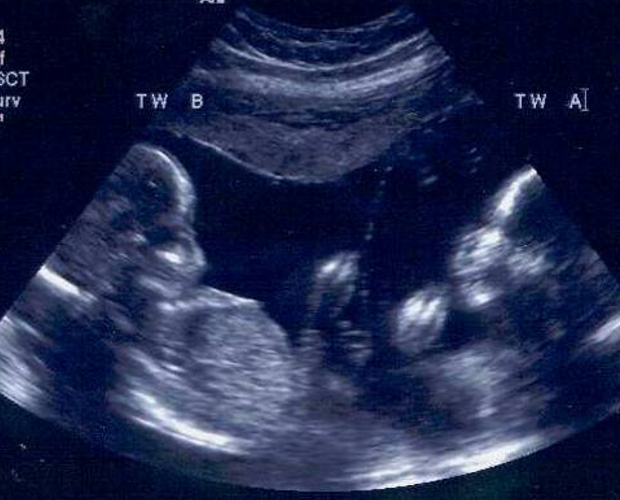

What type of pregnancy?

monochorionic diamniotic - only one chorion